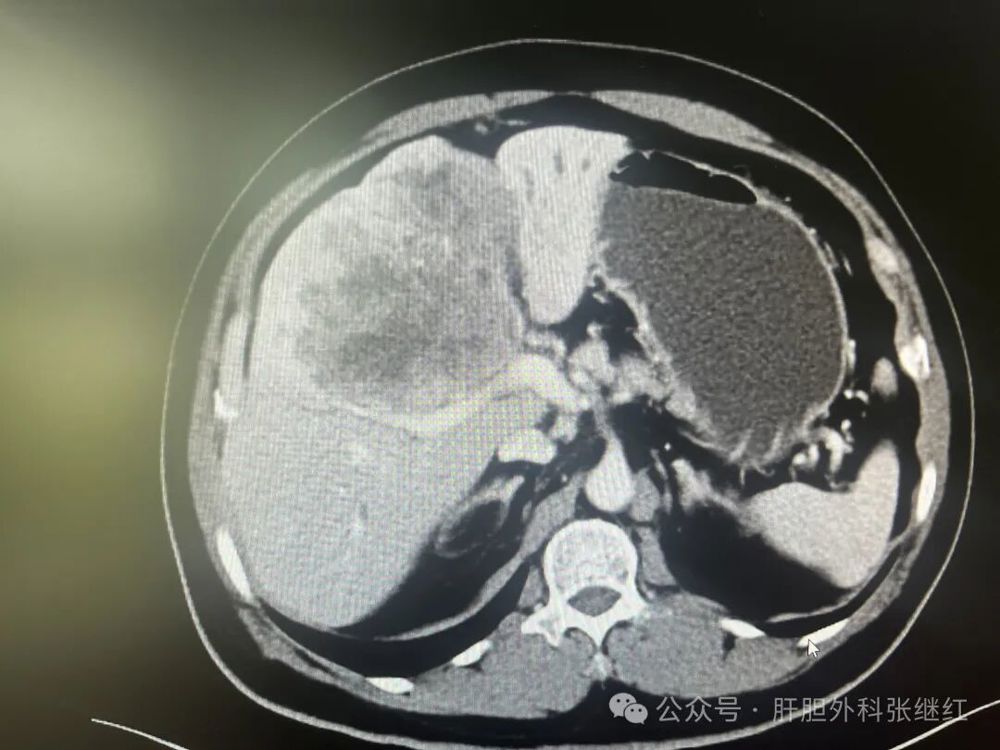

手术前三维重建

该患者是佛山复星禅诚医院肝胆胰外科病例,张继红医生有幸参加了术前多学科会诊和手术。1年前,一男性56岁病人,经CT、MR等影像学检查和病理活检确诊为胆管细胞癌,瘤体巨大,长径超过10厘米,且伴门静脉左支癌栓形成和多发腹腔淋巴结转移,经多学科会诊后决定应用吉西他滨和奥沙利铂化疗联合PD-L1单抗(度伐利尤单抗)免疫治疗进行转化治疗后再手术切除。经上述化疗联合免疫治疗五个疗程(每次均为单次给药,间隔时间21天)治疗后肿瘤明显缩小,直径约5厘米,淋巴结病灶也有所减少或缩小,达到了影像学部分缓解和手术切除的标准,经多学科会诊后决定行扩大左半肝切除及区域淋巴结清扫术,术后再行辅助治疗。本为腹腔镜手术,术中见左肝肿瘤萎缩明显,肿瘤压迫右侧肝蒂,肝门部及肝总动脉周围未见明显肿大淋巴结,肝门部粘连严重,仅清扫12a、12b、7-9组淋巴结所在区域脂肪淋巴组织,解剖离断左肝动脉、门静脉左支及左肝管,发现肿瘤基本位于缺血范围内,超声引导下在缺血线和S5段肿瘤外侧画切肝线,拟切除包括胆囊的S5段和左半肝,15+5min模式间歇性阻断肝门,沿预切线离断肝实质,达右肝蒂时发现肿瘤紧贴右肝蒂,为避免右肝蒂损伤,中转开腹完成整块切除包括胆囊的S5段及左半肝。手术后病理证实肿瘤100%坏死,清扫淋巴结亦未发现肿瘤细胞,达到病理学完全缓解(pCR)。术后早期肝断面少许积液,经引流后积液消失。目前病人状态良好,已无瘤生存半年余。